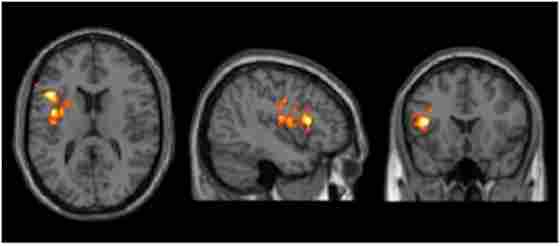

Results of cerebral blood flow (CBF) voxel based comparison superimposed on T1 image. Bipolar disorder (BD) participants showed a CBF increase in left inferior frontal gyrus from T1 to T2 after cognitive training, p < 0.05 (FWE cluster corrected) and k ≥ 11,592 mm3.